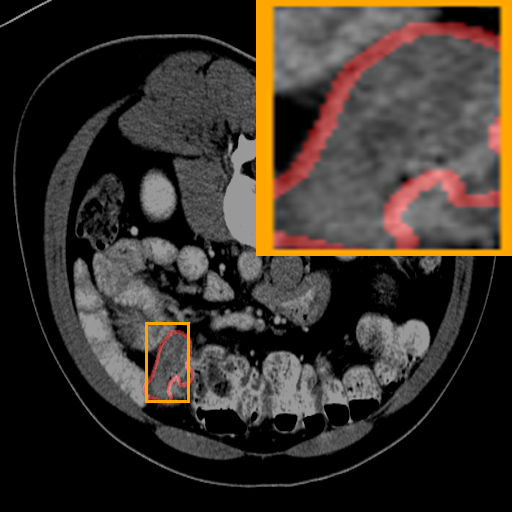

Figure 3: Qualitative comparison visualization of DEAP-3DSAM and baselines on four datasets.

IV-B2 Qualitative Performance Comparison

We also performed qualitative analysis on four datasets. As illustrated in Fig. 3, DEAP-3DSAM accurately identifies the target regions and closely matches their size. In contrast, 3DSAM-Adapter [3dsamadapter] exhibits limitations in matching the size and shape of the target regions. This proves that DEAP-3DSAM captures more complex image features, owing to its Dual Attention Prompter and Feature Enhanced Decoder. Furthermore, while these SAM-based methods are nearly capable of localizing the target regions, many traditional methods, i.e. UNETR++ [unetr++], Swin-UNETR [swinunetr], and TransBTS [transbts], struggle to achieve this. This highlights the potential of SAM-based methods for addressing complex 3D segmentation tasks.